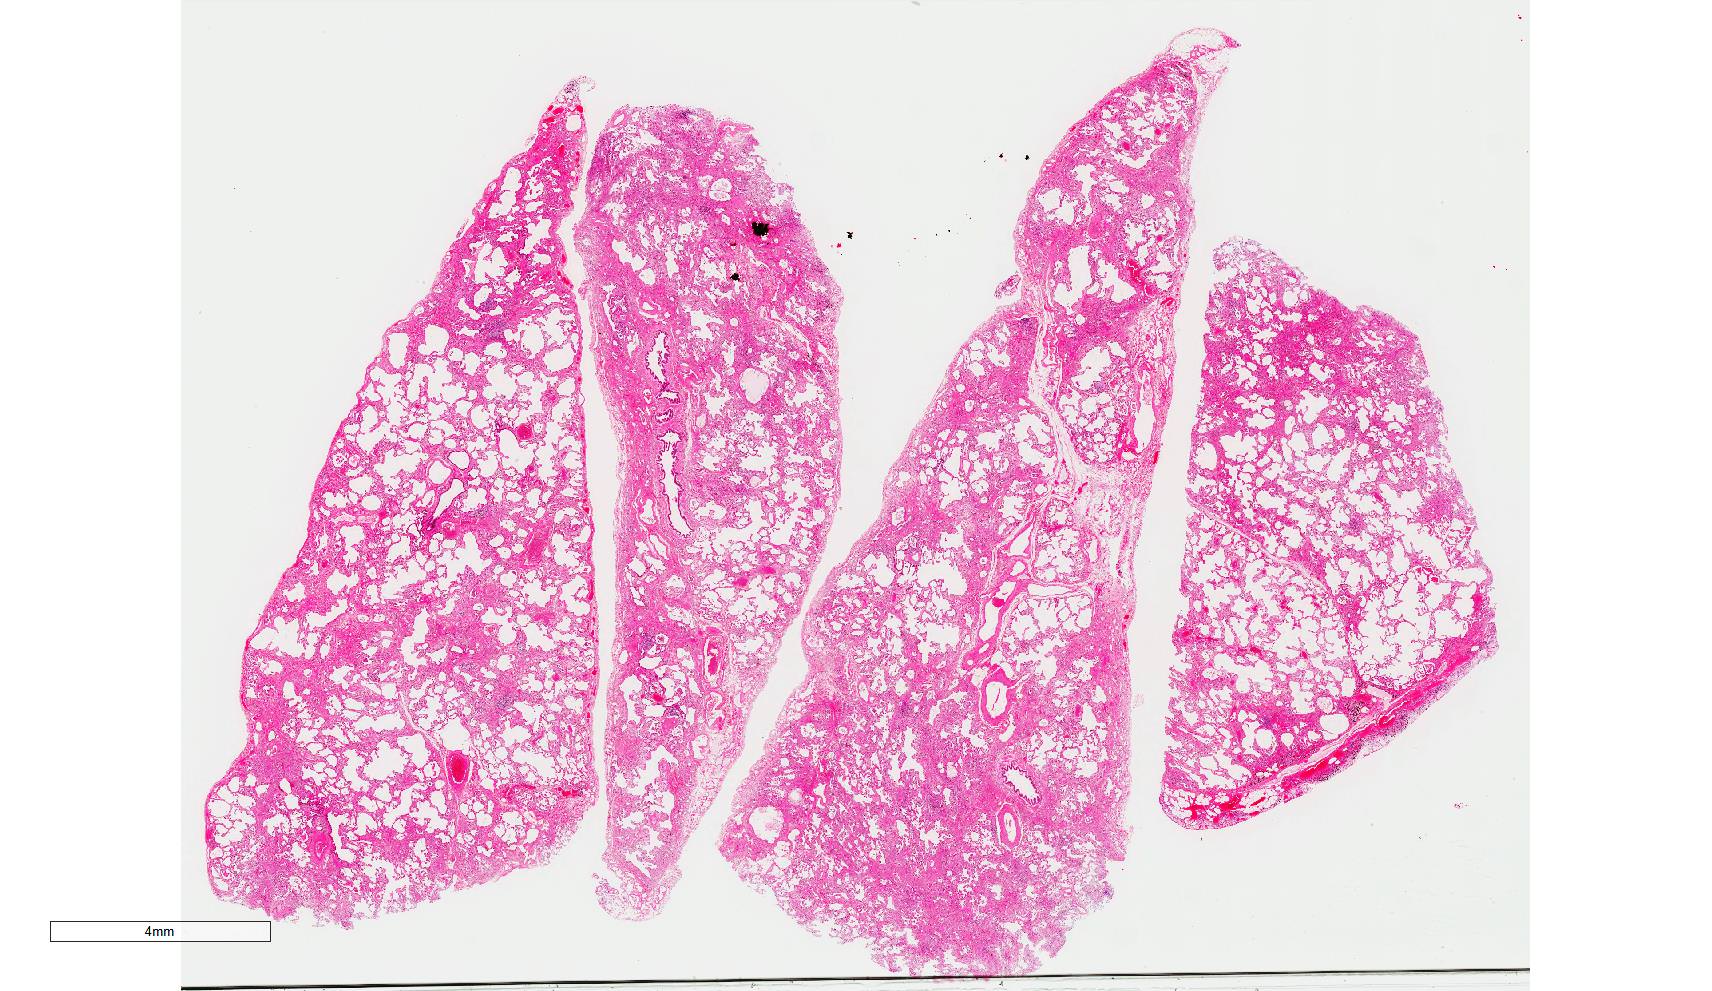

Microscopic (histologic) images

Scroll to see all images.

Contributed by Akira Yoshikawa, M.D.

Gross description

- Diffuse involvement with mild to moderate increase in lung weight

- Fibrotic changes in lower lobes

- Homogeneous and diffuse compared to UIP

- Shrunken lung

- Traction bronchiectasis can be seen

- Honeycomb change can be seen but limited

Microscopic (histologic) description

- Since there are few specific findings for NSIP pattern, it is essential to exclude other lung diseases on histology (Am J Respir Crit Care Med 2008;177:1338)

- Characteristic findings of NSIP pattern

- Diffuse and uniform inflammation ("temporal homogeneity") on low power of alveolar wall, bronchovascular bundles and pleura

- There are usually no normal alveolar walls in the affected lobules

- Cellular or fibrotic change

- Lymphocytic or plasmacytic infiltration

- Loose fibrosis

- Lung architecture is frequently preserved

- "Cellular NSIP" or "fibrotic NSIP" can be stated specifically in pathologist report

- Diffuse and uniform inflammation ("temporal homogeneity") on low power of alveolar wall, bronchovascular bundles and pleura